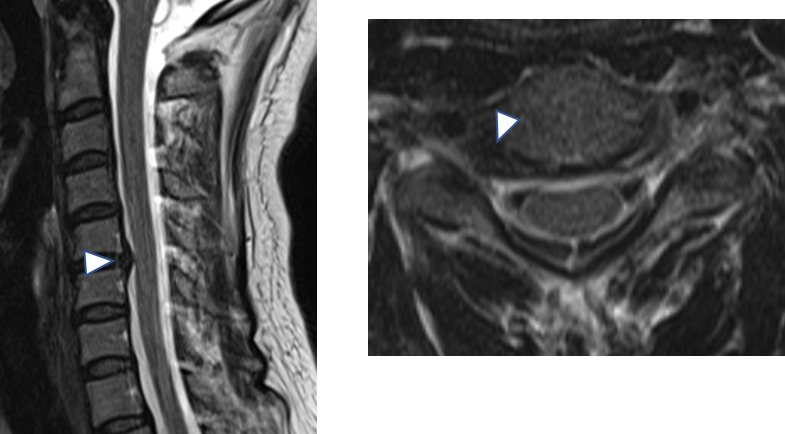

- CT(コンピュータ断層撮影)スキャン

- MRI (磁気共鳴画像法)スキャン

これらの検査により、医師は椎間板の形状やサイズなど、脊椎の骨や構造を直接調べることができます。

乾燥した椎間板は小さく、または薄く見える場合があり、骨自体が互いに擦れ合うと損傷があるように見える場合があります。